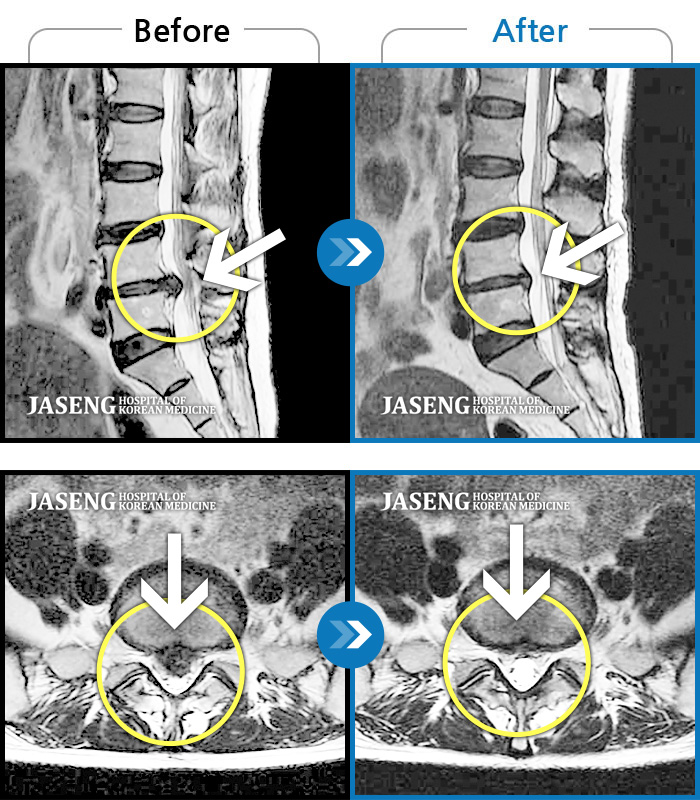

허리디스크

안산 · 김민수 원장

왼쪽 허리에서 다리로 내려가는 심한 통증으로 서 있거나 오래 걷지 못하였습니다.

촬영시기

2022.02.12 ~ 2023.02.17

2023.02.24

조회수 325